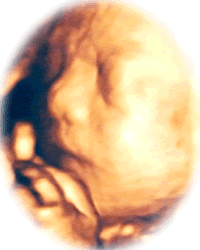

おなかの中の赤ちゃんを見てみませんか?

赤ちゃんの位置により見え方は様々ですが、

おなかの中でのご様子をご家族で感じていただけます。

3D/4Dエコー撮影

3D/4Dエコーでは、妊婦健診の時に見ている超音波の画像(2Dエコー)よりも分かりやすく、赤ちゃんを立体で表現し、動いている様子もご覧いただけます。顔立ちや表情、手足の動きなどをご出産前に感じていただけます。

赤ちゃんがお顔をみせてくれた時、タイミングが良いと、大きな口を開けているところが見られることもあります。また、「今のは蹴ったんだね!」など、胎動と画面がリンクする体験ができるかもしれません。

7ヶ月(24週~27週)

身長:約35cm

体重:約1000g

手でお顔を隠したり、ママのおなかにパンチやキックをしている姿を見ることができます。

8ヶ月(28週~31週)

身長:約40cm

体重:約1500g

この頃になると皮下脂肪がついてお顔がふっくら丸みをおびてくるのがわかります。

口をパクパクさせている様子がみえるかもしれません。